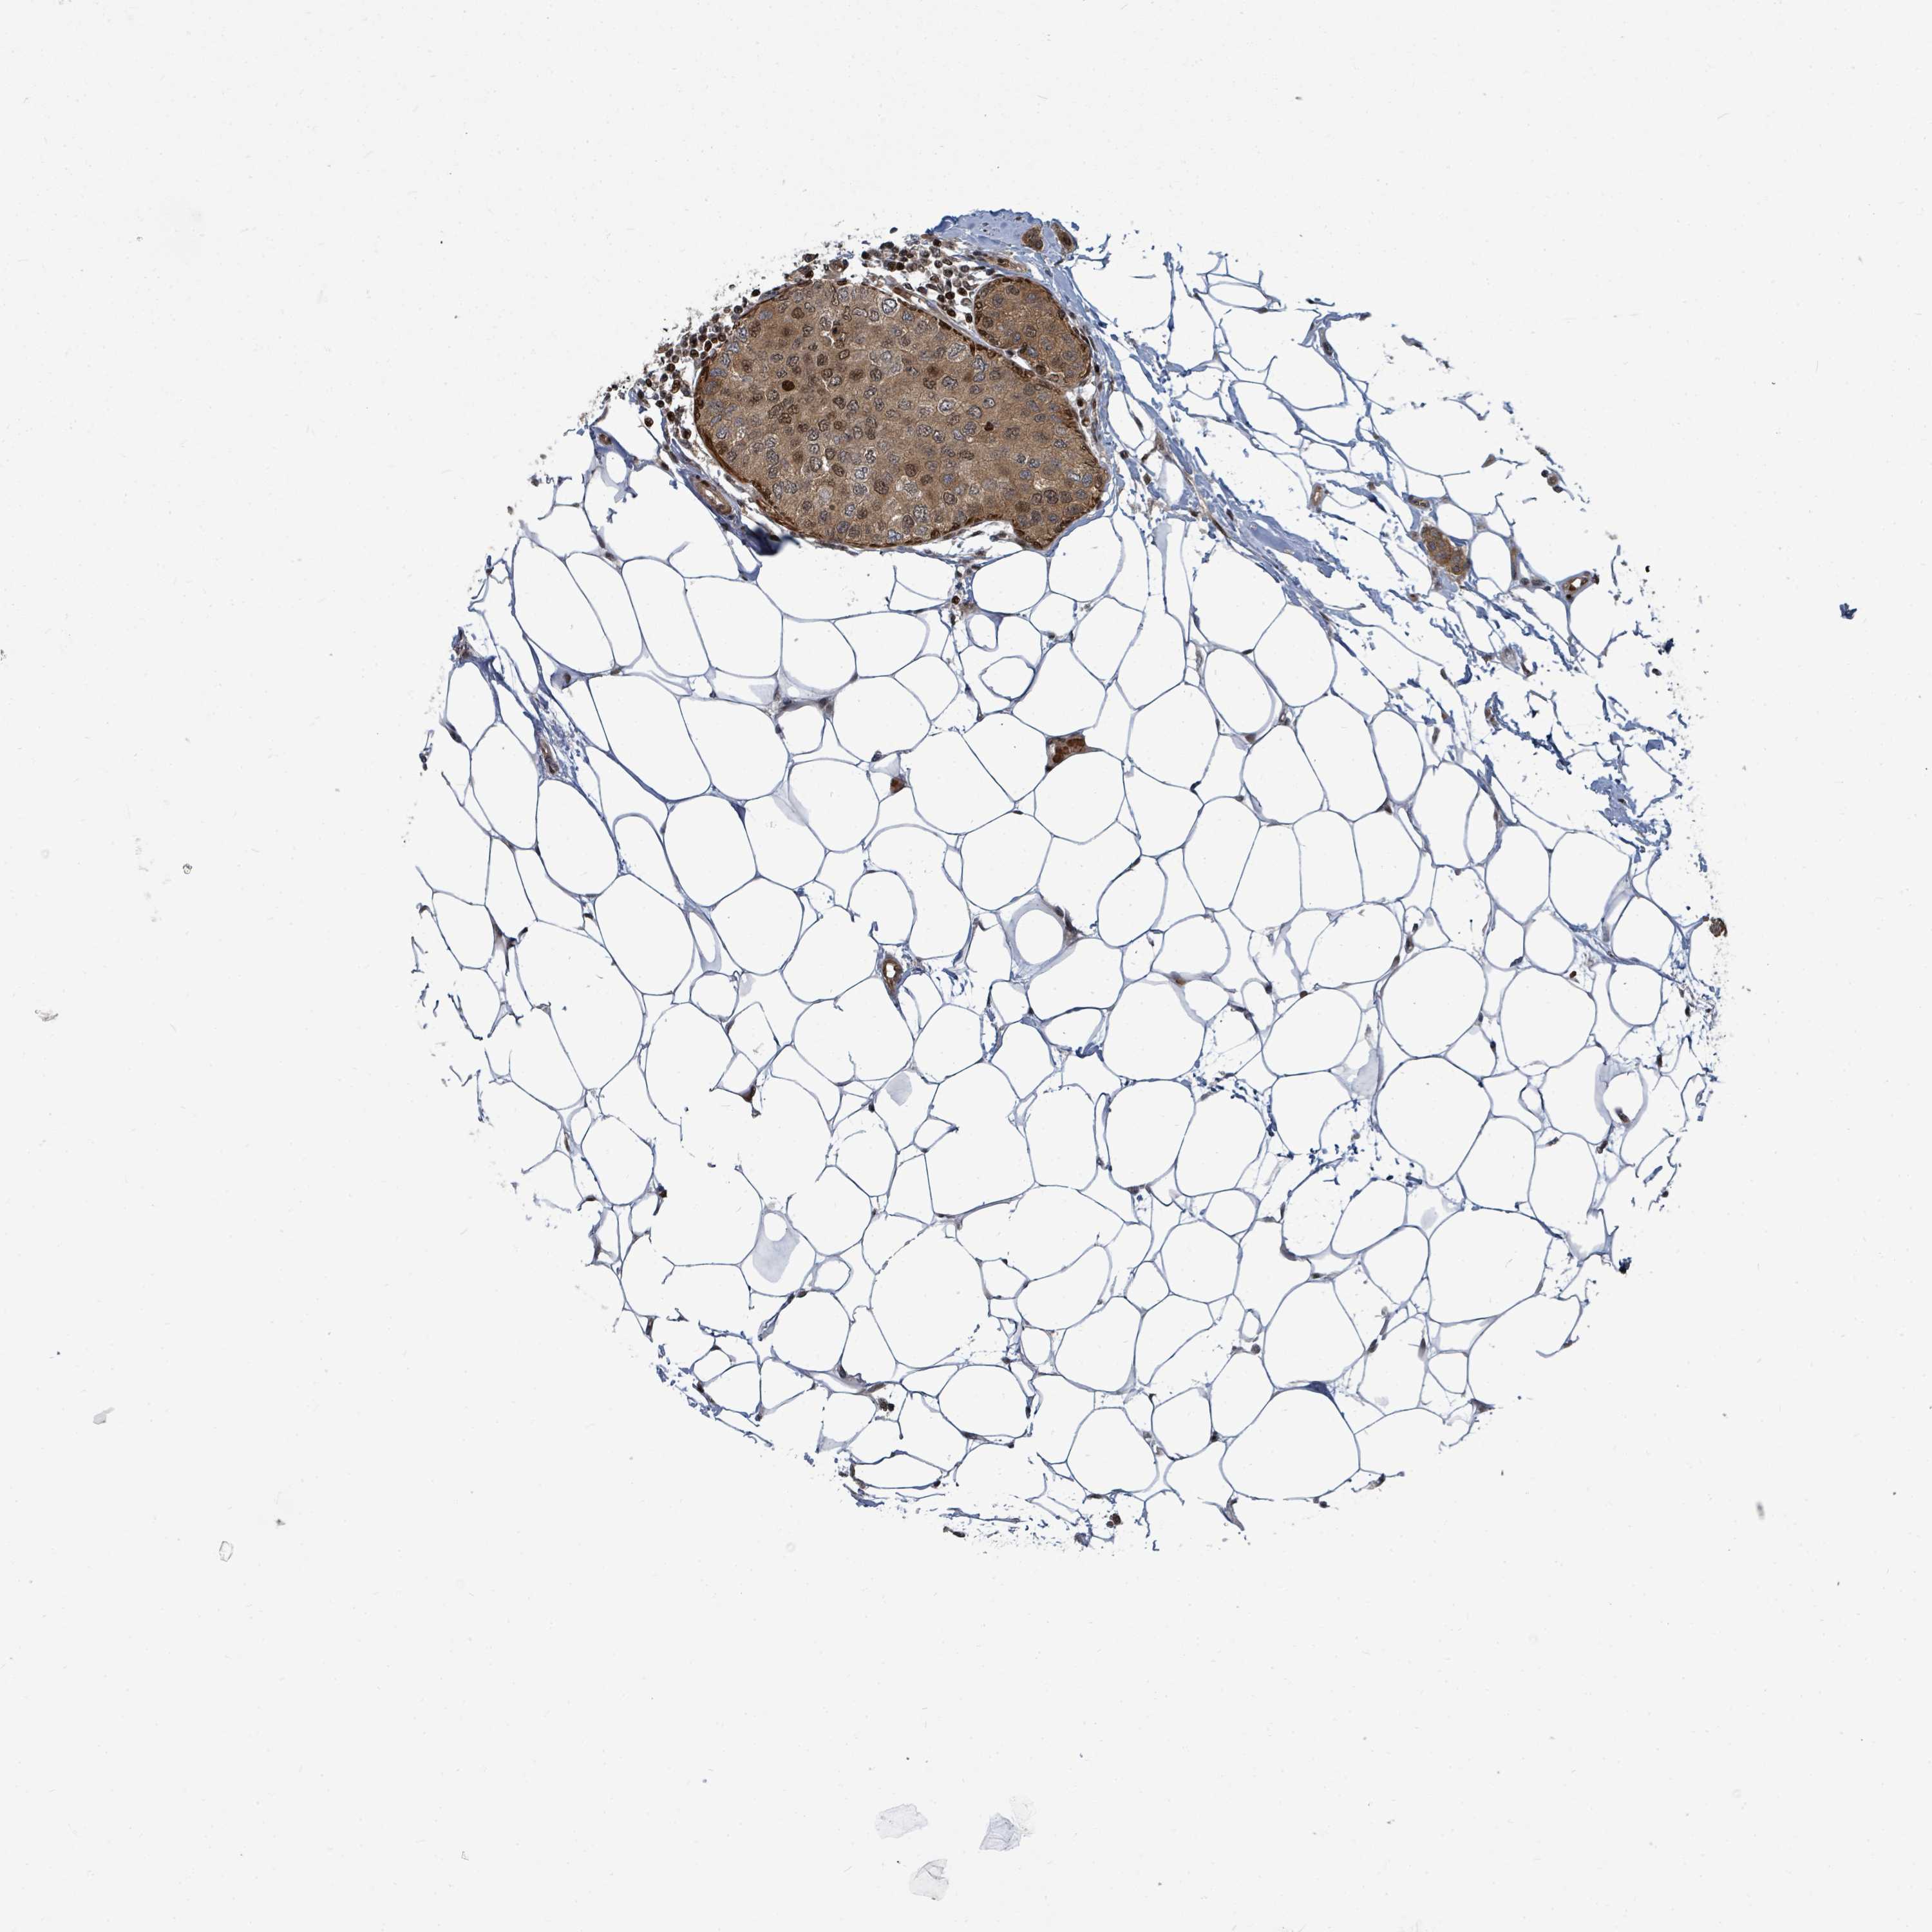

CANCER BREAST CANCER Show tissue menu

BRCA TCGA BRCA VALIDATION PROTEIN EXPRESSION